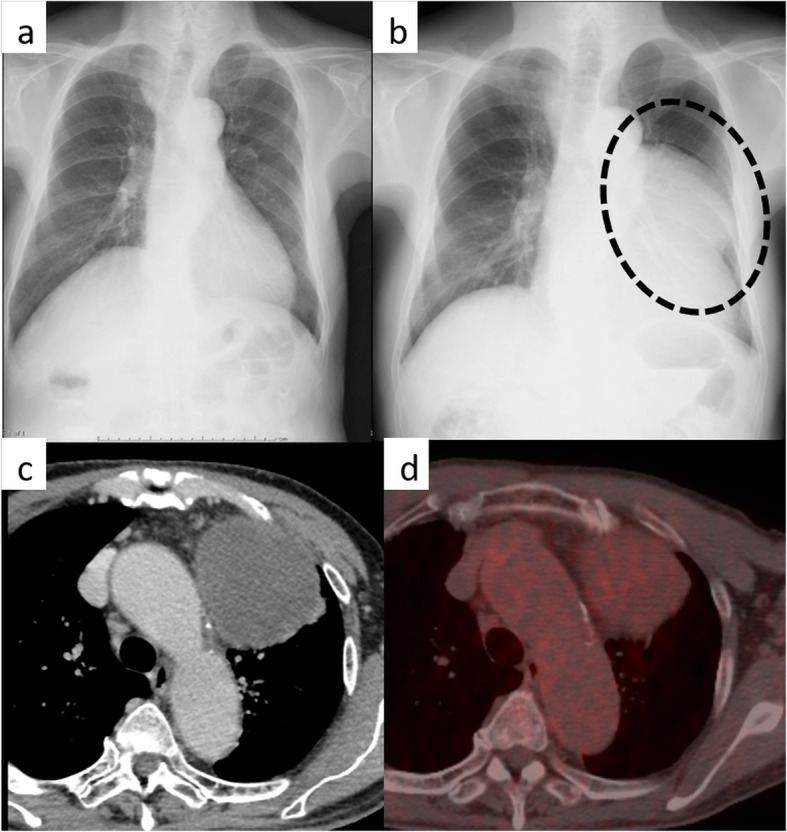

A 77-year-old man with a chief complaint of persistent dry cough had an abnormal giant mass on chest radiography (CR) and was referred to our hospital. There were no remarkable findings noted during the physical examination and in blood test results including tumor markers. The giant mass occupied the left-sided mediastinum on CR; however, there was no abnormal finding on the previous year’s CR (Fig. 1a, b). Chest-enhanced computed tomography (CT) revealed a well-circumscribed 11-cm mass in the left-sided anterior mediastinum (Fig. 1c). The mean CT value of the mass was 40 Hounsfield units (range, 20–70), and there were no areas of fatty density. Positron emission tomography-CT showed accumulation of fluorodeoxyglucose uptake in the tumor, with a maximum standard uptake value (SUVmax) of 3.3 (Fig. 1d). We preoperatively diagnosed the benign tumor as a thymoma, solitary fibrous tumor (SFT), or neurogenic tumor, or as a malignant tumor such as thymic cancer, based on the radiological evaluation.

Fig. 1.

Chest radiography showing the mass (b: dotted circle). The mass was not observed a year ago (a). Chest-enhanced computed tomography showing an approximately 11-cm mediastinal tumor occupying left internal cavity (c). Fluorodeoxyglucose-positron emission tomography showing accumulation in the tumor (maximum standard uptake value = 3.3) (d)